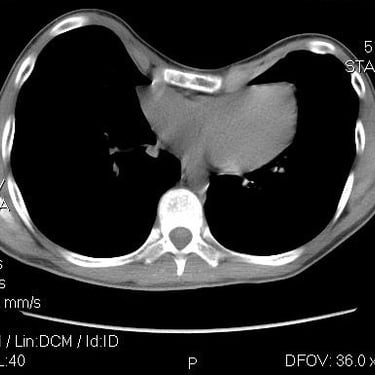

Assessment begins with a thorough paediatric history and examination, focusing on evidence of underlying medical conditions, cardiorespiratory symptoms, other conditions that might explain these symptoms, and psychological impact. Underlying or comorbid conditions are investigated and treated, and we work with a comprehensive network of professionals to assess the physiological impact of chest wall variations, with tests including (but not limited to) computed tomography, echocardiography, lung function testing and cardiopulmonary exercise testing. Depending on the outcome of these we signpost to support groups such as Pectus Matters and refer for non-surgical (e.g. the Vacuum Bell) and surgical treatments (via the national MDT) where appropriate.